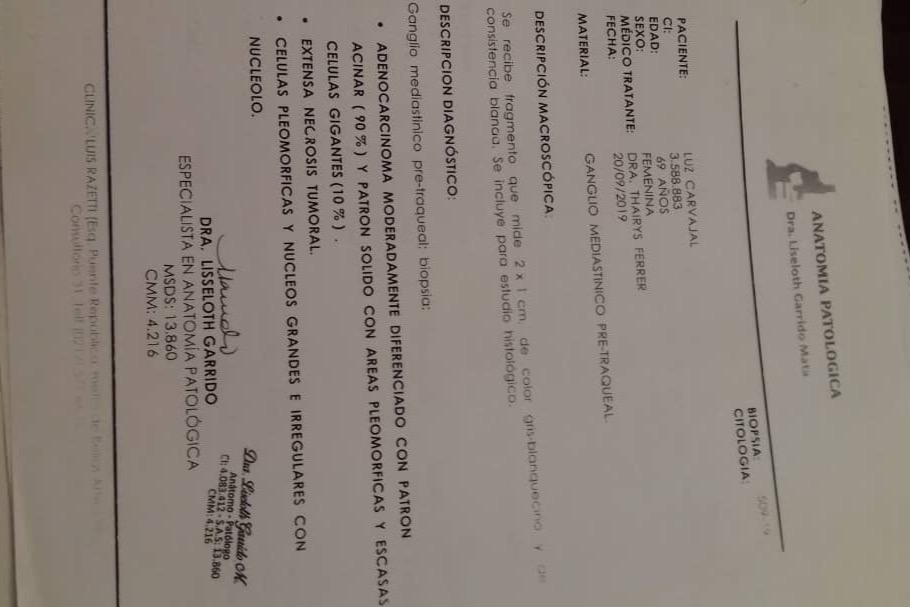

En septiembre de 2019 fue diagnosticada con cáncer de pulmón con una Lesión Ocupante de Espacio (LOE) de 2,5 cm y otra lesión en el Mediastino de 5,4 x 4,7 cm.

A continuación les dejo el diagnóstico, los exámenes, y los presupuestos de los próximos exámenes que hay que hacerle a mi mamá.

In September 2019, she was diagnosed with lung cancer with a Space Occupying Injury (LOE) of 2.5 cm and another lesion in the Mediastinum of 5.4 x 4.7 cm.

Down here I leave the diagnosis, exams, and budgets for the next exams to be done to my mom.

En septiembre de 2019 fue diagnosticada con cáncer de pulmón con una Lesión Ocupante de Espacio (LOE) de 2,5 cm y otra lesión en el Mediastino de 5,4 x 4,7 cm.

A continuación les dejo el diagnóstico, los exámenes, y los presupuestos de los próximos exámenes que hay que hacerle a mi mamá.

In September 2019, she was diagnosed with lung cancer with a Space Occupying Injury (LOE) of 2.5 cm and another lesion in the Mediastinum of 5.4 x 4.7 cm.

Down here I leave the diagnosis, exams, and budgets for the next exams to be done to my mom.